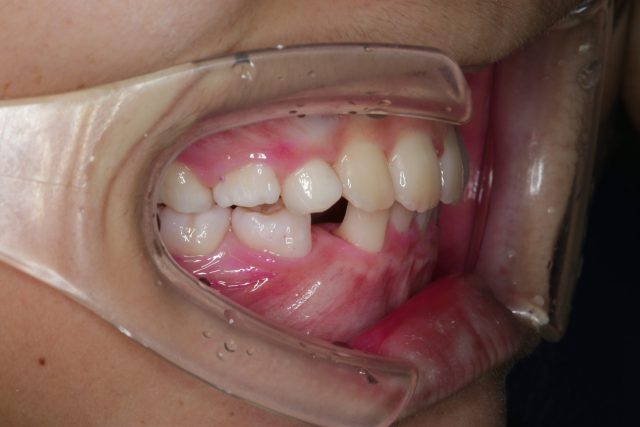

8歳男の子インビザラインファースト:永久歯スペース不足を解消

| 年齢・性別・主訴 | 8歳男の子 永久歯が並ぶスペースが足りない |

| 治療方法 | インビザラインファーストを使用し(1日20時間以上の着用) 、問題点の改善を行なった。 |

他のBefore